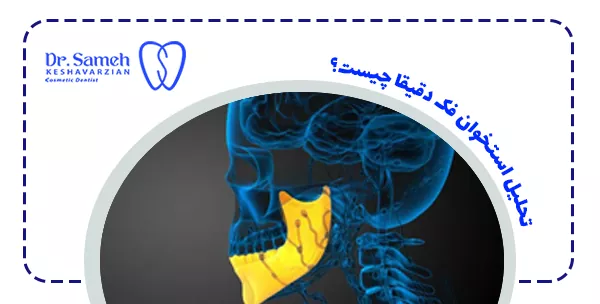

تحلیل استخوان فک دقیقا چیست؟

تحلیل استخوان فک به فرآیندی گفته می شود که طی آن بافت سخت استخوانی اطراف دندان ها یا ناحیه فک به مرور دچار کاهش حجم می شود. این پدیده معمولا پس از دست رفتن دندان یا در نتیجه بیماری های لثه آغاز می شود. استخوان فک نقش مهمی در نگهداشتن دندان ها و حتی شکل صورت دارد، بنابراین تحلیل آن می تواند علاوه بر مشکلات عملکردی، ظاهر صورت را نیز تغییر دهد. زمانی که یک دندان از دست می رود، فشار طبیعی که هنگام جویدن به استخوان وارد می شود کاهش می یابد. نبود این فشار باعث می شود سلول های استخوانی کمتر تحریک شوند و در نتیجه استخوان فک شروع به تحلیل رفتن کند.